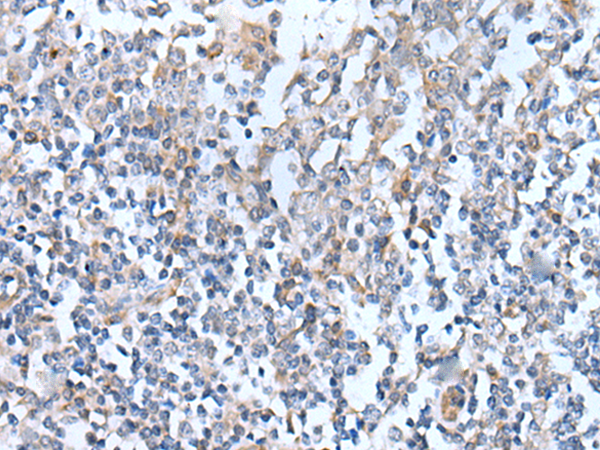

分类: 科研抗体货号: P12740别名: SCYB5; ENA-78应用: IHC反应种属: Human